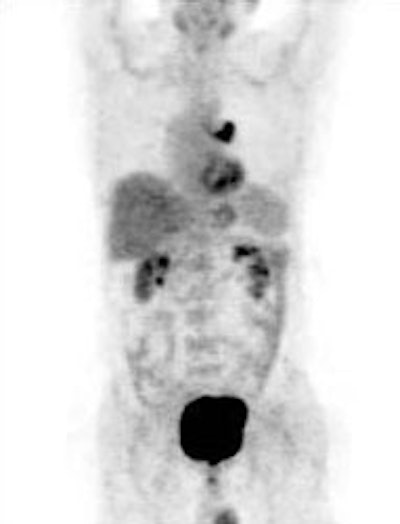

Unsuspected bone metastases: The patient shown below had a left lung non-small cell lung cancer (vaguely seen in the left lung on the PET images shown below). There was no uptake of tracer within the hila or mediastinum to suggest nodal metastases, however, unsuspected bone metastases were found in the right humerus and right hip (black arrows). These findings significantly altered patient management. |

|

Unsuspected bone metastases: The patient shown below had a cavitary left lung non-small cell lung cancer. There was no uptake of tracer within the aortopulmonary window lymph nodes detected on CT to suggest metastases, however, unsuspected bone metastases were found in the left anterior 4th rib (black arrow) and lumbar spine (red arrows- not included in staging lung CT scan). The presence of bone metastases significantly alters patient prognosis and management. PET imaging provides a rapid whole body survey for the detection of unsuspected metastatic disease. |